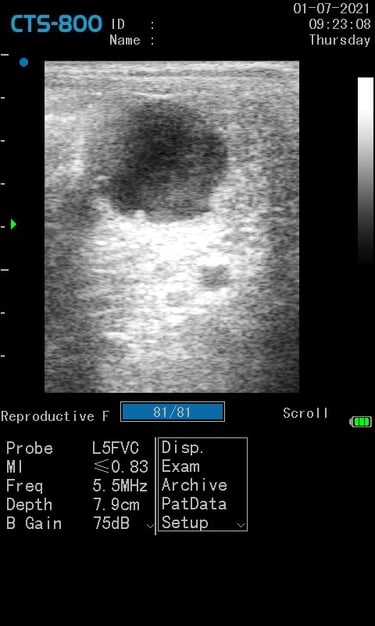

Gynécologie